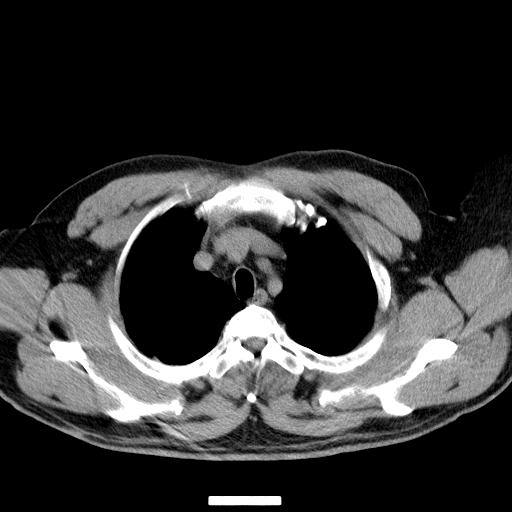

标题: CT25454:男,51岁,体检时发现右上纵隔高密度影。请会诊! [打印本页]

标题: CT25454:男,51岁,体检时发现右上纵隔高密度影。请会诊!

男,51岁,体检时发现右上纵隔高密度影。

右上纵隔脊柱旁圆形结节,密度均匀,边界清楚——考虑神经源性肿瘤!